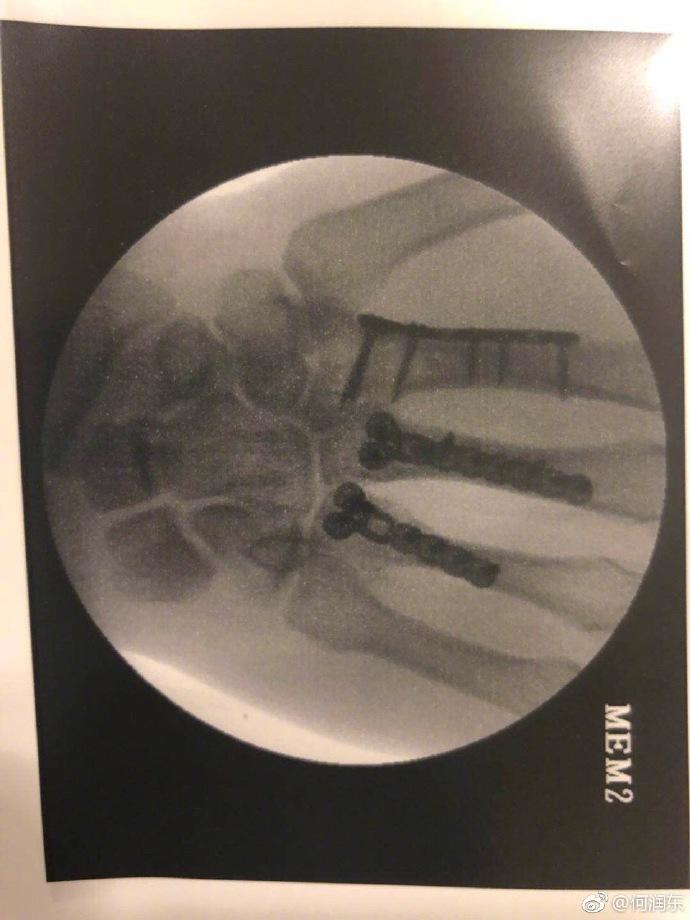

他受伤的伤情才不止这一点,另一张X光片明显看得出来有三根手指都做了固定处理。黑乎乎的阴影,看着也是让人毛骨悚然。